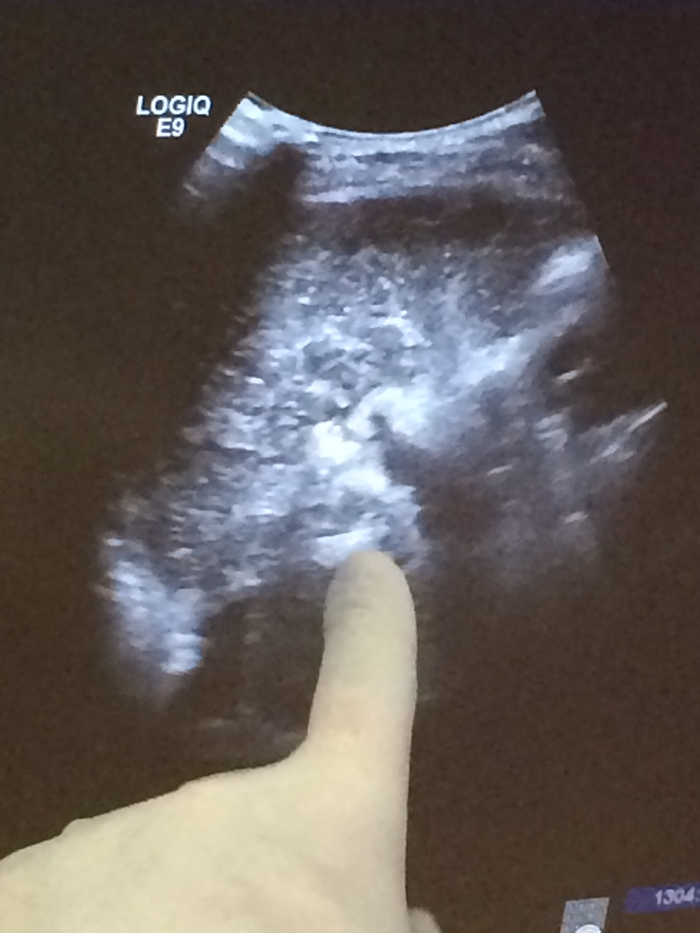

術(shù)中彩超定位尾狀葉腫塊

??? 近日,毛大爺接受了這項治療。在超聲引導(dǎo)下,由皮膚直接插入細針直達尾狀葉腫瘤瘤體,通過射頻能量徹底破壞腫瘤。治療過程不到半小時,體表除了一個難辨的針眼外沒有留下任何疤痕。術(shù)后當天就下床活動,第三天行動自如。